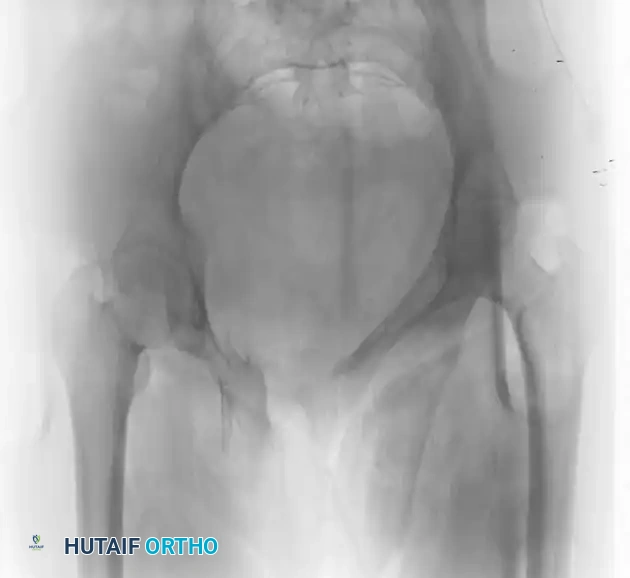

FIGURE 56-47 & 56-48: Denis classification of sacral fractures, differentiating three zones of injury: Zone I (sacral ala), Zone II (foraminal region), and Zone III (spinal canal). The most medial fracture extension classifies the injury. Accompanied by 40-degree caudal inlet and 40-degree cephalad outlet views of the pelvis.